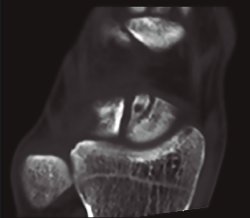

Figura 4. Fractura del polo proximal del escafoides por vía abierta dorsal.

La vía dorsal abierta estaría indicada en fracturas del polo proximal del escafoides (Figura 4); se aborda la cápsula entre el extensor largo del pulgar y los tendones radiales. Es la vía ideal para las fracturas de polo proximal y permite la colocación de un tornillo más centrado en el eje del escafoides(20).